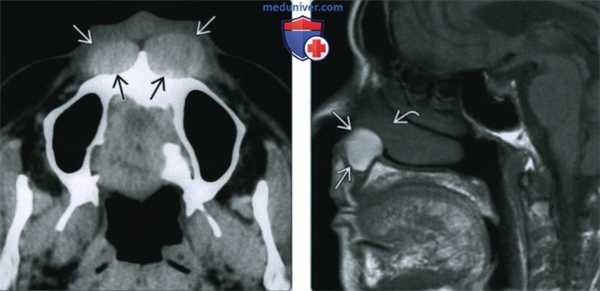

(Слева) При аксиальной КТ без контрастного усиления спереди от предчелюстной кости (с обеих сторон) визуализируются гиперденсные объемные образования округлой формы с четкими контурами. Образования вызвали выраженное ремоделирование верхней челюсти (больше слева). Носогубные кисты являются двухсторонними менее чем в 10% случаев.

(Справа) При МРТ Т1ВИ в сагиттальной проекции визуализируется носогубная киста с диффузно гиперинтенсивным сигналом, хорошо отграниченная от окружающих тканей. Обратите внимание, что верхний край кисты расположен в непосредственной близости к нижней носовой раковине и дну преддверия носа. При исследовании этих образований обнаружено, что они имеют подслизистую локализацию.

(Слева) При MPT Т1 в аксиальной проекции в пределах грушевидною отверстия визуализируется хорошо отграниченное объемное образование, распространяющееся в преддверие носа. Сигнал от образования слегка интенсивнее, чем от мышц, определяются фокусы гиперинтенсивною сигнала (белковый дебрис). Обратите внимание, что объемное образование вплотную прилежит к верхней челюсти и вызывает ее умеренно выраженную эрозию по сравнению с противоположной стороной.

(Справа) При MPT Т2 ВИ FS в аксиальной проекции визуализируется носогубная киста округлой формы с сигналом равномерной интенсивности, содержащая белковый дебрис со слегка гипоинтенсивным сигналом.